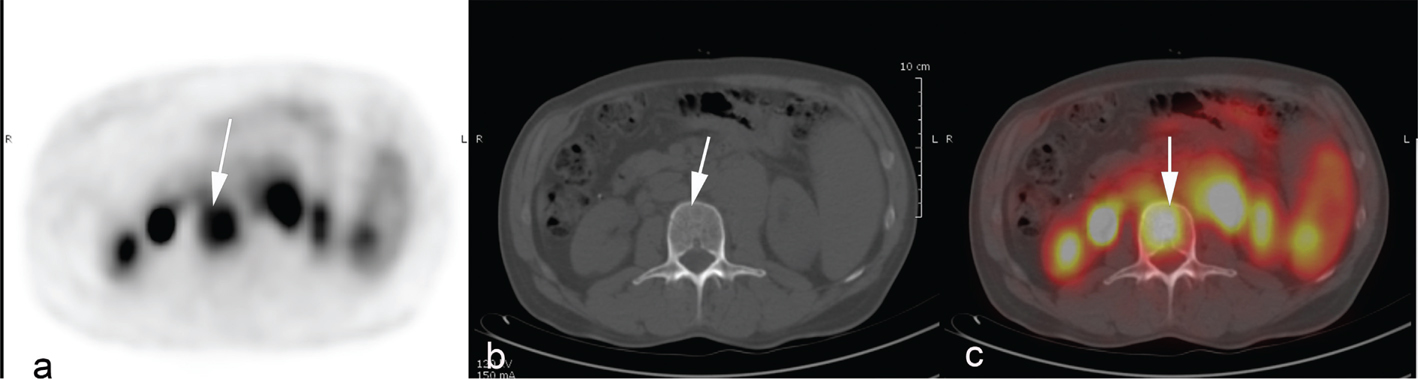

Fig 5

Figure 5. Metabolic tumor volume measurements with volume delineation using the SUV41% thresholding method (a) and SUV2.5 thresholding method (b). The total metabolic tumor volume (including all the lesions) was 91ml with the 41%SUVmax method vs 250ml with SUV>2.5.